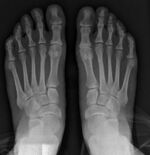

![]() Fig. 8a. Painful hallux valgus and metatarsus primus varus deformity recurrence of left foot after osteotomy surgery | |

Late deformity recurrence can happen after osteotomy (bone-breaking) procedures because osteotomy surgeries do not specifically stabilize first metatarsal bone.

For recurrence correction after fusion procedure (Fig. 9) Metatarsus primus varus deformity and pain recurred 6 months after modified Lapidus procedure and it could also be again corrected by the syndesmosis procedure.